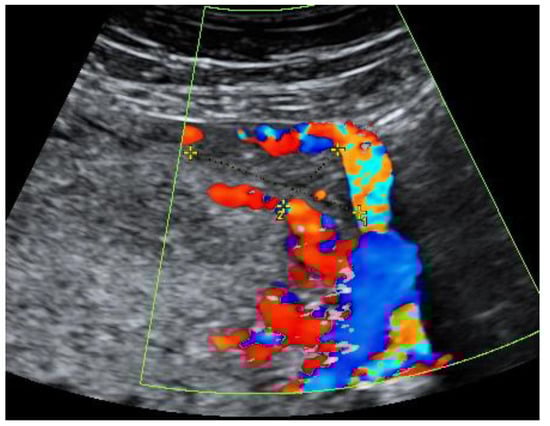

During hospitalization, blood and urine tests’ results were within the normal range. A multidisciplinary team (MDT) decided to keep monitoring the growth of both pregnancies by ultrasound while maternal vitals were stable and noted that further management would be determined according to the clinical situation. On the third day of hospitalization the patient started to feel more severe pain in the hypogastric region, radiating to the back and the left groin. The MDT made a decision to perform a diagnostic laparoscopy. Laparoscopy confirmed heterotopic angular pregnancy in the left enlarged, swollen cornu of the uterus. The left ovary and fallopian tube were not damaged and there were no signs of uterine rupture. Figure 3 and Figure 4.

Medicina 57 01207 g003

Figure 4. Left cornu of the uterus, observed during diagnostic laparoscopy.